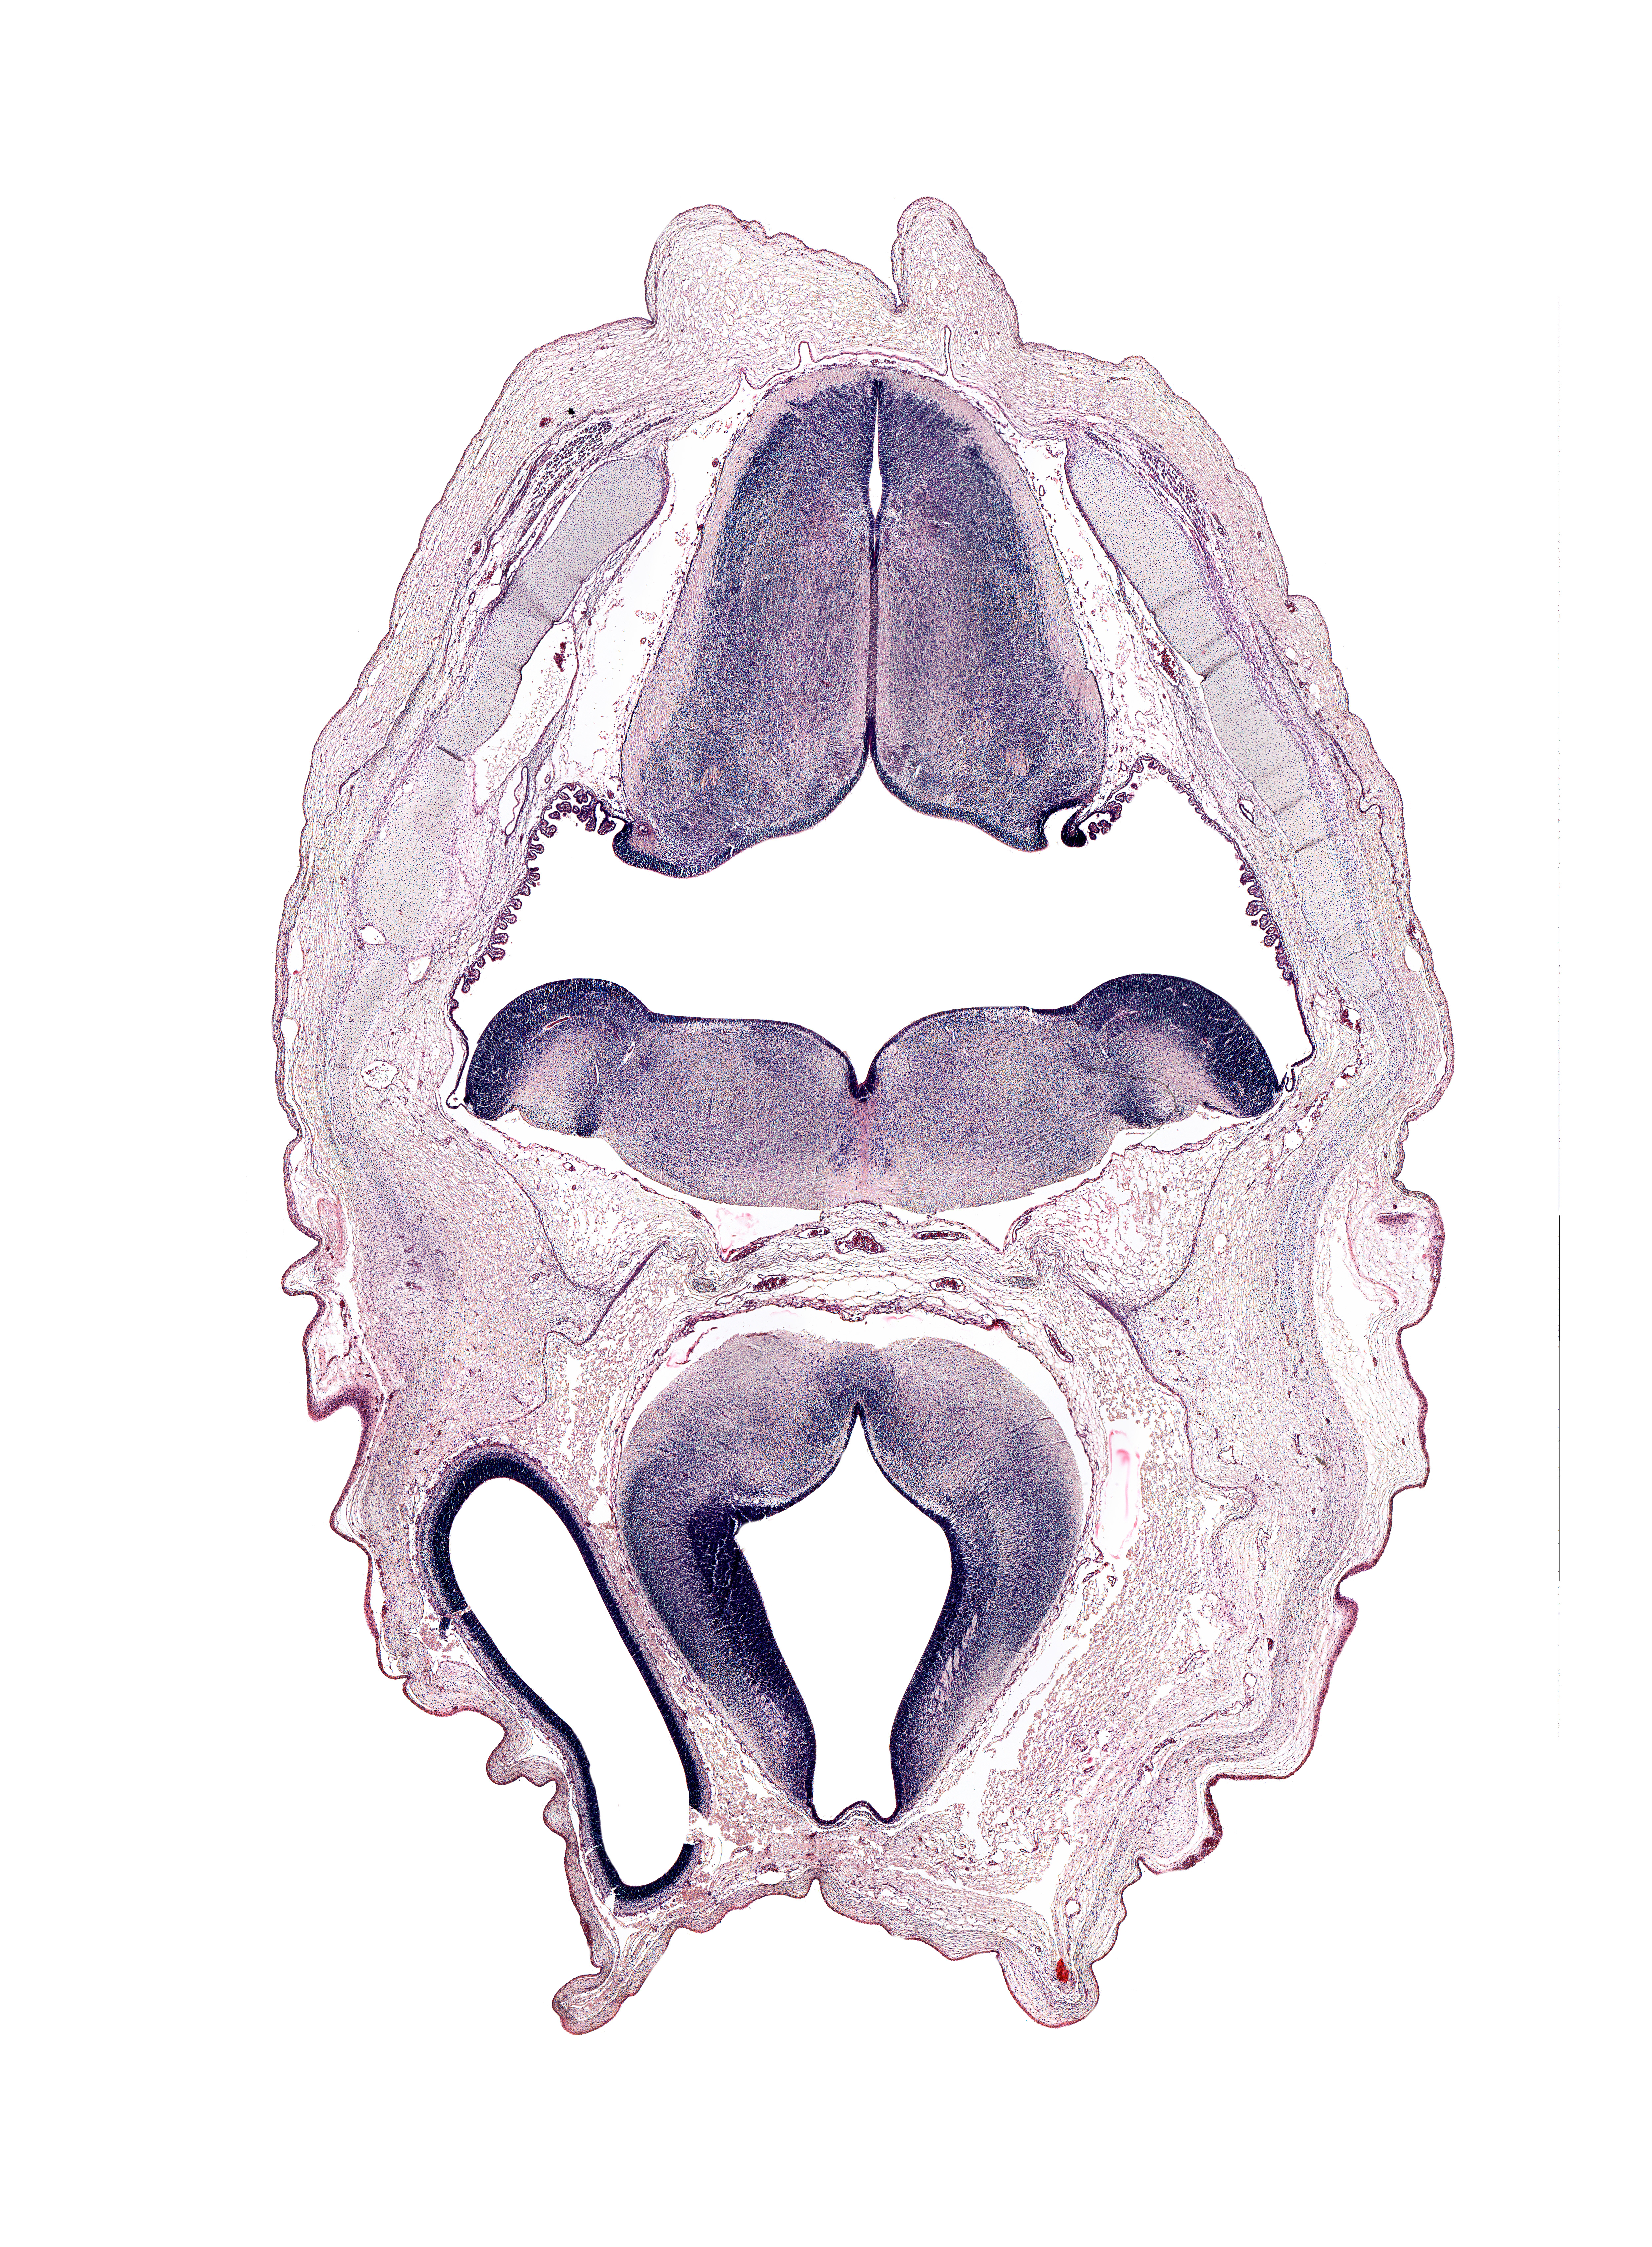

Boyd Embryo #H983 | Location: 37-1-4

Keywords: artifact space(s), basilar artery, cephalic edge of endolymphatic sac, cerebral vesicle (hemisphere), dural band for tentorium cerebelli, hypoglossal nucleus, intermediate zone, marginal zone, middle dural venous plexus, myelencephalon (medulla oblongata), osteogenic layer, rhombencoel (fourth ventricle), sulcus limitans, tegmentum of pons, tract of vestibulocochlear nerve (CN VIII), ventricular zone

Source: The Virtual Human Embryo.